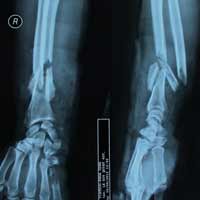

Theo các bác sĩ, bệnh nhân nhập viện trong tình trạng bị chấn thương rất phức tạp ở vùng khuỷu tay trái, phần gân tay bị đứt, da tay và một phần xương khuỷu tay bị biến dạng. Hiện bệnh viện đang tiến hành các phẫu thuật cần thiết để cứu lấy phần cánh tay của anh Nhẫn. Tuy nhiên, nếu phần cánh tay tổn thương bị nhiễm trùng thì tỉ lệ để giữ lại cánh tay là rất thấp và có thể phải tiến hành tháo khớp tay.